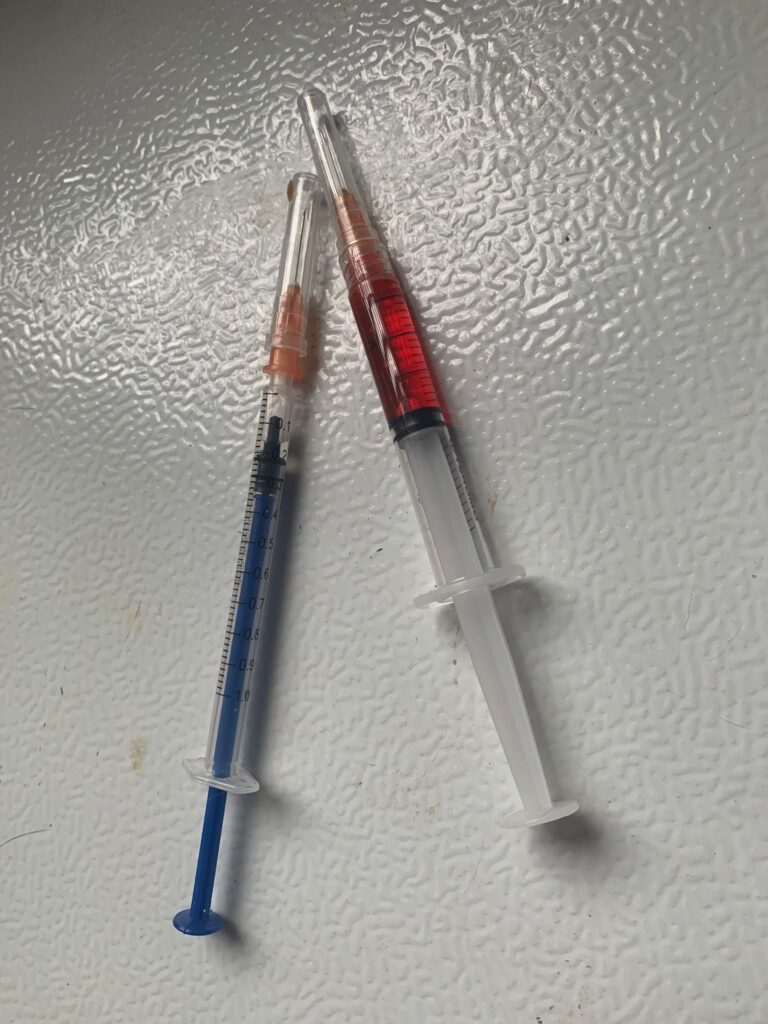

Prepare his fercosang jab to be given Tmr

11Am+: given Subcut, b com n b12 and fercosang. He is still on f patch, wipe his face

Morning: major cleaning day. Subcut him n given b12 b com jab. His f patch drop off le. Given bupre. Still love selar

2pm+: checked on him, is right ear got one line, quite deep, bleeding but alr stop. Will give him 5 days ab 0.2ml clav to play safe. Given Subcut n bupre 0.2ml. 3.99kg – gain 80g in a month. Got walk about to eat

10am+: b4 I Subcut n give painkiller still eating ok. Subcut and given b12 b com bupre and put on a f patch (end 1.3.24)

Noon: 3.91kg – lose 210g in 1 week. Subcut him w B12 n b com. N bupre. More vocal but in pain can’t think of reason to go clinic other than status check

Morning: given Subcut w b12 b com. N bupre

Morning: Subcut w b12 and Buprenophine

Morning: Subcut w b12 and Buprenophine

Morning: Subcut w b12 and bupre.

Day; he looks v unwell, pain? Eyes nose mouth discharge, clean him up. Up his bupre 0.2ml and fercosang given.

Given sc, bupre, fer, b12 and b com, doxy.

Subcut w b12. N bupre. Given Cerenia drops